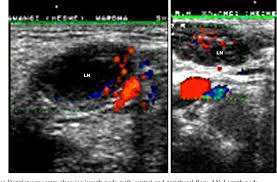

Enlarged Lymph Nodes In Head And Neck Cancer Analysis With Triplex Ultrasonography Sathyanarayan V Siva Bharani K Ann Maxillofac Surg from www.amsjournal.com Ultrasound an ultrasound is sometimes used, especially to look at the thyroid, salivary glands and lymph glands in the neck. Ultrasonography of neck lymph nodes; As thyroid cancer gets more advanced, you might notice symptoms like: Lumps can also form in the lips. A small lump on the neck usually is a lymph node, a small sebaceous cyst or a lipoma, although it could be something else. Reactive lymph nodes look different on ultrasound to lymphoma, so i'm sure the report to the gp will be the same as what she told you. Ultrasound is used to see the thyroid gland and the lymph node of the neck. During biopsy, the ultrasound helps make sure they are getting fna samples from the right areas.

The sonographer stands facing the ultrasound and uses their right hand to move the transducer on the patient's neck, thus simultaneously facing both the ultrasound monitor ( on the left) and the patient's face ( on the right) figure 4.5. Are there signs of thyroid cancer on ultrasound? Sounds like they've been enlarged from an infection, maybe fighting one you weren't even aware of. A neck lump or nodule is the most common symptom of thyroid cancer. How a nodule looks on ultrasound can sometimes suggest if it is likely to be a cancer, but ultrasound can't tell for sure. Physical examination/blood and urine tests. Skin cancer is by far the most common type of cancer. An ultrasound of the neck is used to examine the carotid arteries located on each side of a patient's neck. The doctor will also inspect the nose, mouth, throat, and tongue for abnormalities, often using a light and a mirror for a. During a physical examination, the doctor feels for any lumps on the neck, lips, gums, and cheeks. Unfortunately cancer of the thyroid will not show up on an ultrasound. Most of the time, patients in the low risk group are simply monitored by ultrasound. An ultrasound scanner uses high frequency sound waves to create images of the internal soft tissues of the face and neck.

Doctors often use them to guide a needle during a biopsy. Carotid ultrasound tests for blocked or narrowed carotid arteries, which can increase the. If left unchecked, the cancer can break out of the lymph node and spread to the surrounding. This picture gallery contains some examples of the more common. Ultrasound is relatively quick and simple test that gives very useful information about the soft tissues in the head and neck region including the lymph. Thyroid nodules, or lumps, are very common.most aren't cancer. Reactive lymph nodes look different on ultrasound to lymphoma, so i'm sure the report to the gp will be the same as what she told you. Trusted, accurate neck ultrasound, from the experts in anchorage. The doctor will also inspect the nose, mouth, throat, and tongue for abnormalities, often using a light and a mirror for a. Epidemiology it typically presents in younger women with an average age of onset at around 45 y. Malignant cyst look more complex and may have solid areas. Doctors in 147 specialties are here to answer your questions or offer you advice, prescriptions, and more. Two in three cases of thyroid cancer occur in people under age 55, and 75%.